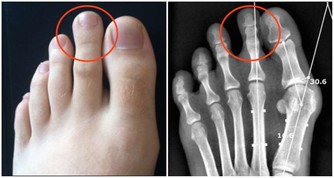

大夫通過腹部平片,醫生發現小曹胃泡脹大、腸腔脹氣明顯。急診科醫生馬上給小曹插了胃管,結果,「噗~」地一聲,胃管裡立即竄出大量氣體!其中還夾雜著漿糊般粘稠的液體和食物殘渣,噴泉即視感有木有?! 小曹一五一十地交代,臨睡前沒少吃 ↓↓↓ 兩包泡麵 一堆土豆塊 兩瓶汽水 零食若幹